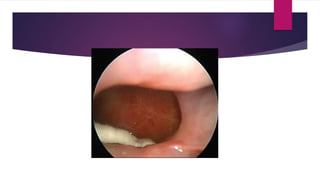

 Anterior rhinoscopy

 Alteration of nasal mucosa appearance

 White discoloration of pale mucosa indicates tissue ischemia secondary to

angiocentric invasion

 Black discoloration indicates tissue necrosis

 Decreased mucosal bleeding

 Anaesthetic regions